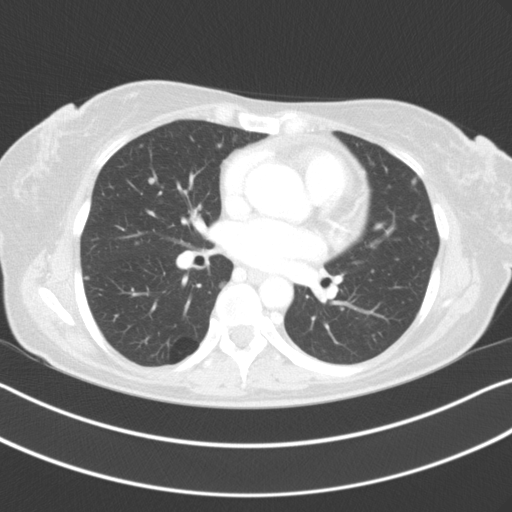

Image Grid

4×3 grid: Rows show different image types (Original NATIVE, Reconstructed NATIVE, Original VENOUS, Generated VENOUS), Columns show windowing techniques (No Window, Lung Window, Mediastinum Window)

Original NATIVE CT scan (input)

Lung window (WL -600, WW 1500 → Low −1350, High +150)

Reconstructed NATIVE CT scan (cycle consistency)

Lung window (WL -600, WW 1500 → Low −1350, High +150)

Original VENOUS CT scan

Lung window (WL -600, WW 1500 → Low −1350, High +150)

Generated VENOUS CT scan (A→B translation)

Lung window (WL -600, WW 1500 → Low −1350, High +150)

Windowing Parameters

- Lung Window: WL -600, WW 1500 → Low −1350, High +150 (optimal for pulmonary structures)